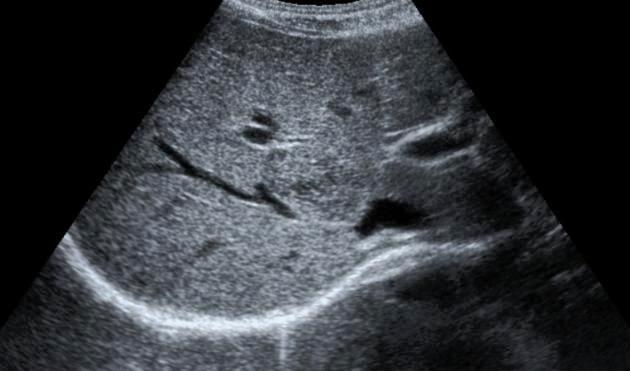

Explain the procedure of a liver exam.

Begin doing a full sweep through the liver. Starting sagittal,

slightly to the left of midline. Change to a transverse view and sweep

up and down the left lobe from a subcostal approach. Look in

transverse through the right lobe subcostally or

intercostally.

Explain the Sagittal plane for the liver exam.

The transducer may be swept under the intercostal margin to image the liver parenchyma from the anterior abdominal wall to the diaphragm.

Explain the Transverse plane for the liver exam.

The transducer should be angled in a steep cephalic direction to be as parallel to the diaphragm as possible. The transverse plan allows images of liver parenchyma, vascularity and ductal structures.